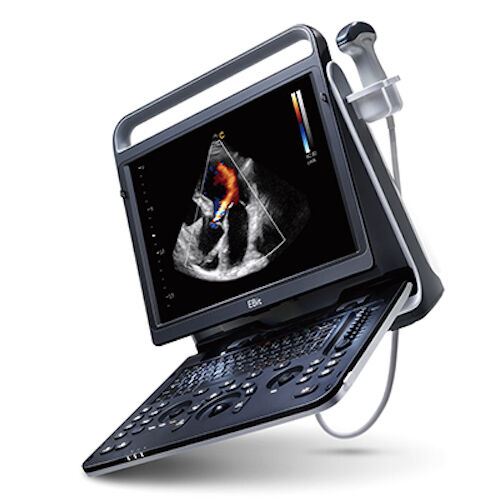

Save $ 2,933.88

DIAGNOSTIC ULTRASOUND MACHINES FOR SALE

Chison eBit 60 Color Doppler Ultrasound Scanner CW w/ Cardiac and Linear Probes

Sale price$ 13,365.42

Regular price$ 16,299.30